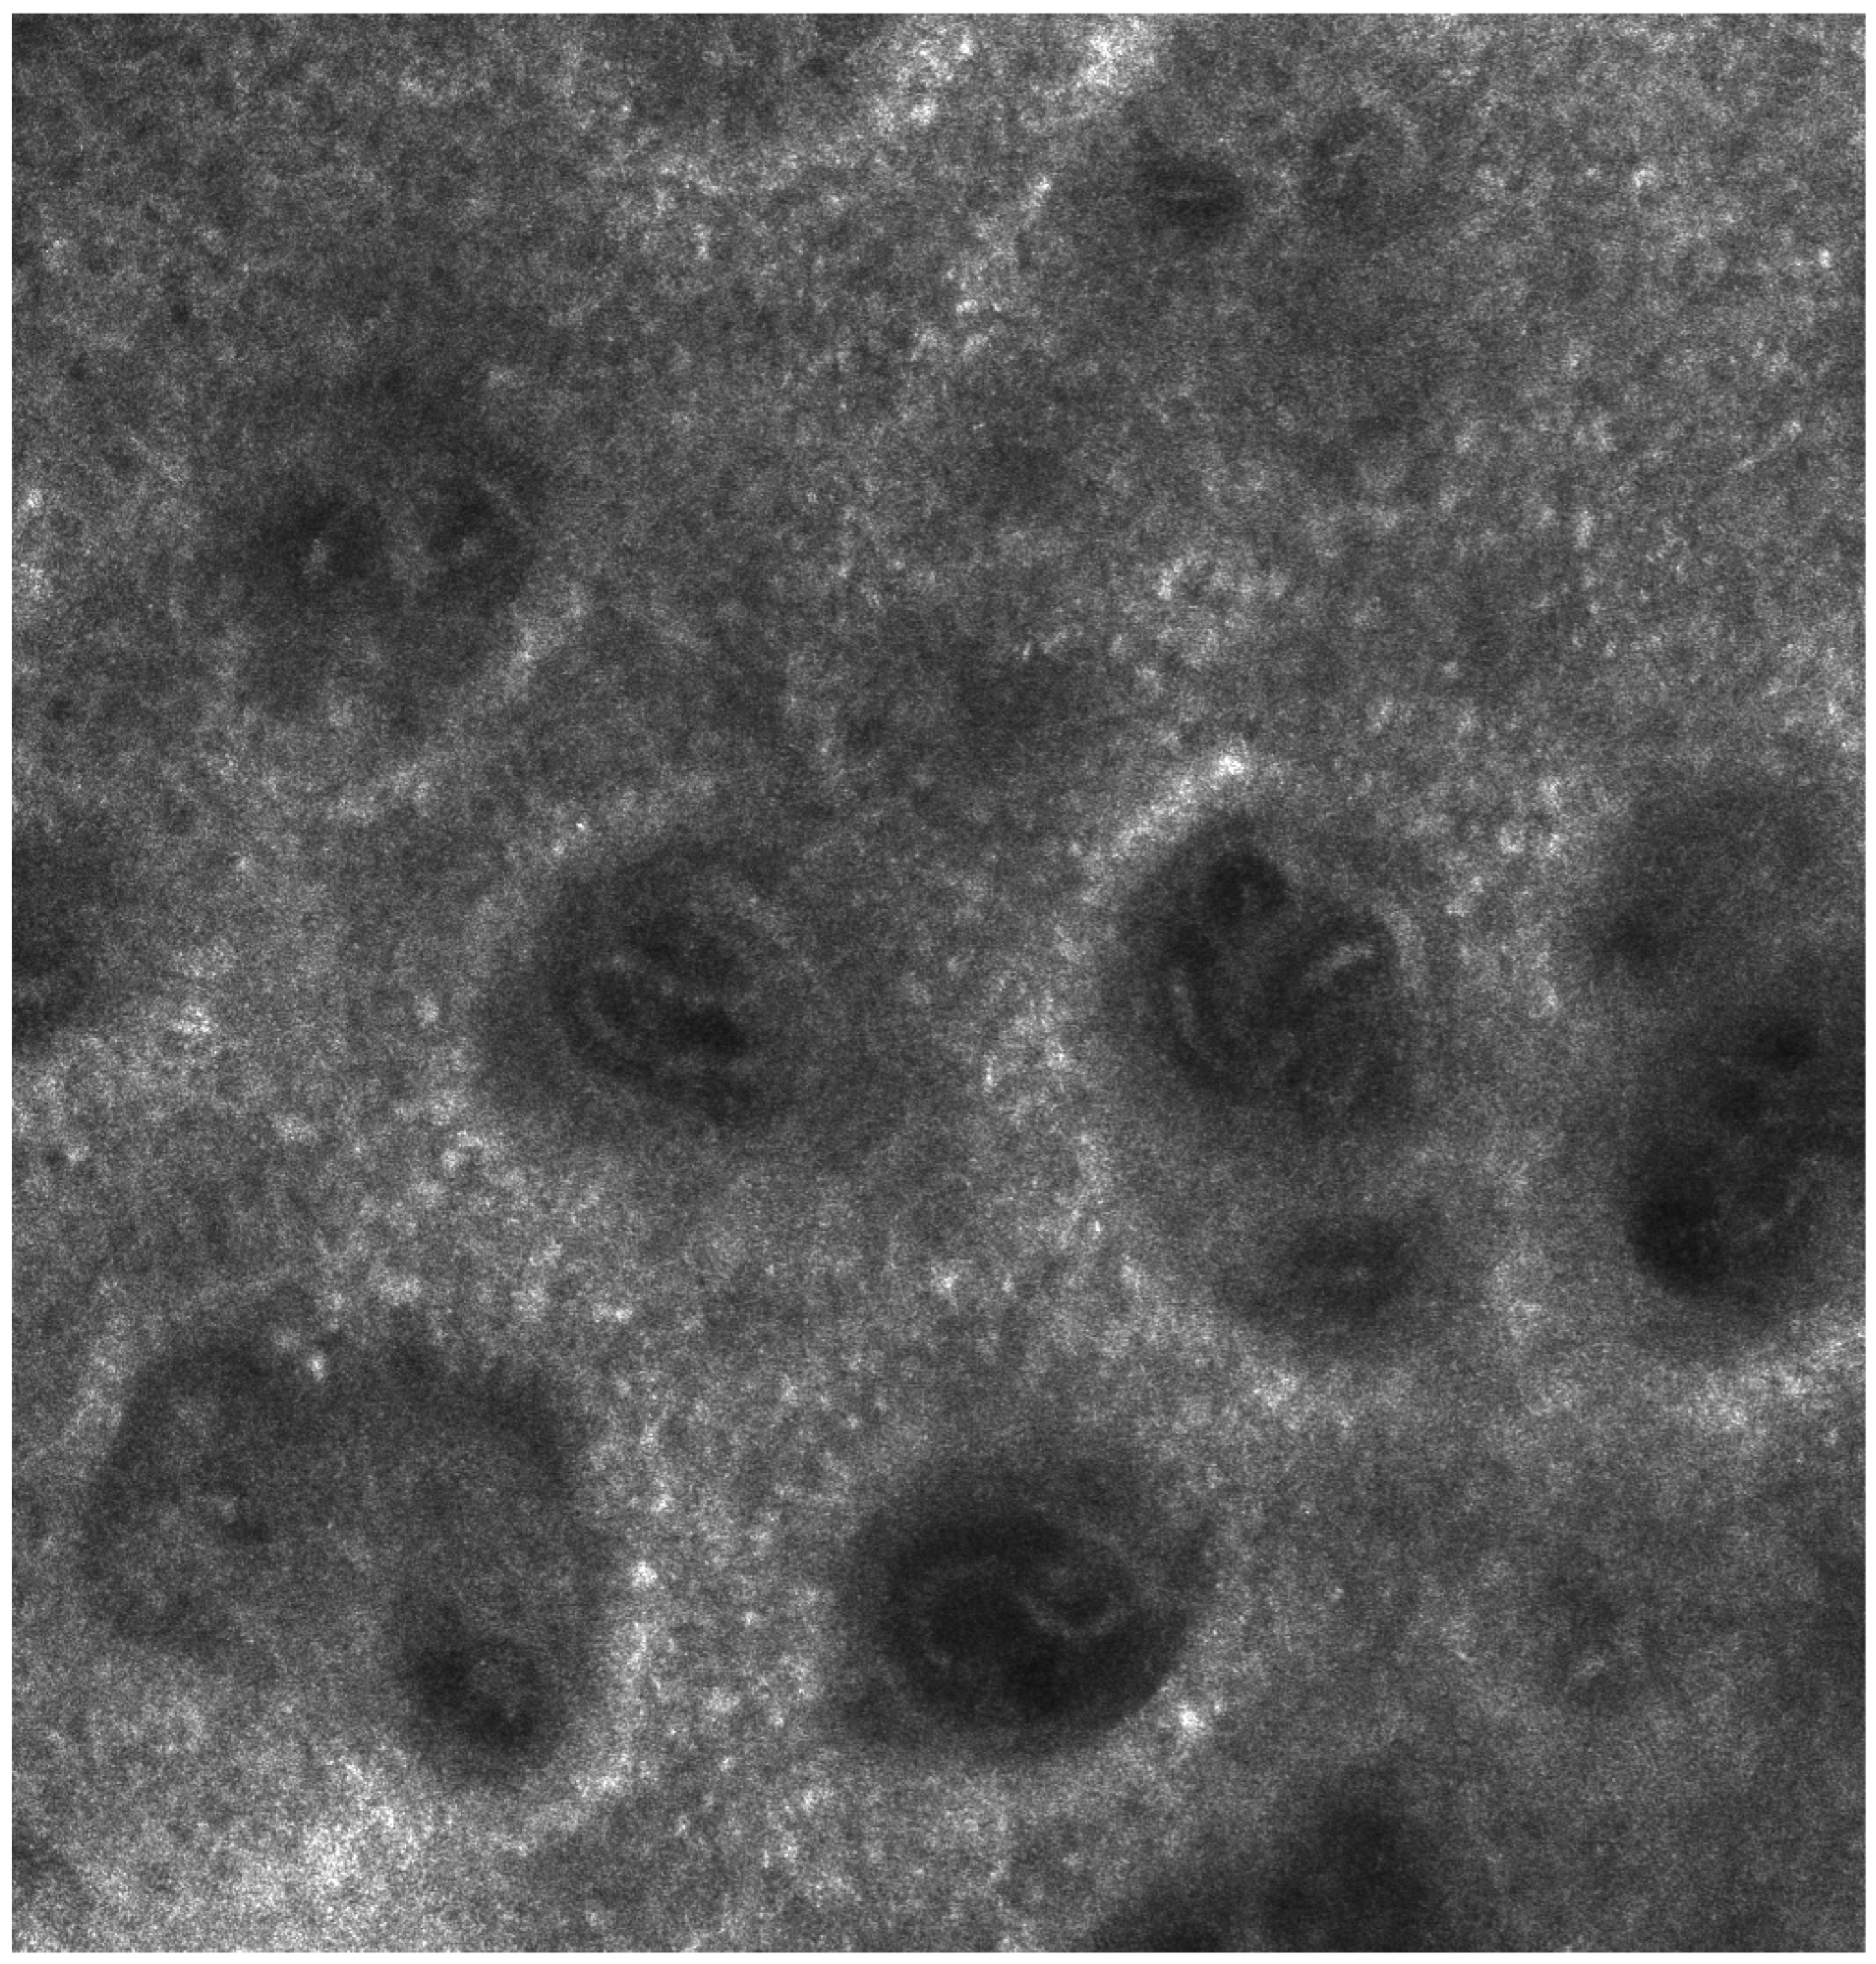

As biologic therapy reduced inflammation and psoriatic plaques began to clear, the “edged papillae” feature became visible again, suggesting a normalization of epidermal renewal. This change indicates that blocking IL-23 and IL-17 helps restore the balance of the epidermal microenvironment, allowing melanocytes to resume interleukin secretion and regain normal function. These findings support the idea that chronic inflammation in psoriasis disrupts not only keratinocyte proliferation but also the dermo-epidermal structure, thereby affecting melanocyte homeostasis [78].

These observations highlight the potential of confocal microscopy as a valuable tool for tracking treatment response, offering objective markers of epidermal restoration and melanocyte function. The reappearance of “edged papillae” with biologic therapy also reinforces the idea that epidermal regeneration and melanocyte activity are closely linked to cytokine balance, which may explain post-inflammatory hyperpigmentation and lentiginous changes in psoriasis patients (Figure 3 and Figure 4).

Figure 3. Reflective confocal microscopy aspect of a psoriasis plaque 3 months after treatment initiation—reappearance of the edged papillae structure, alongside a reduction in inflammation and papillomatosis.

Figure 4. Reflective confocal microscopy aspect of a psoriasis plaque 6 months after treatment initiation—reappearance of the edged papillae structure, alongside a reduction in inflammation and papillomatosis.